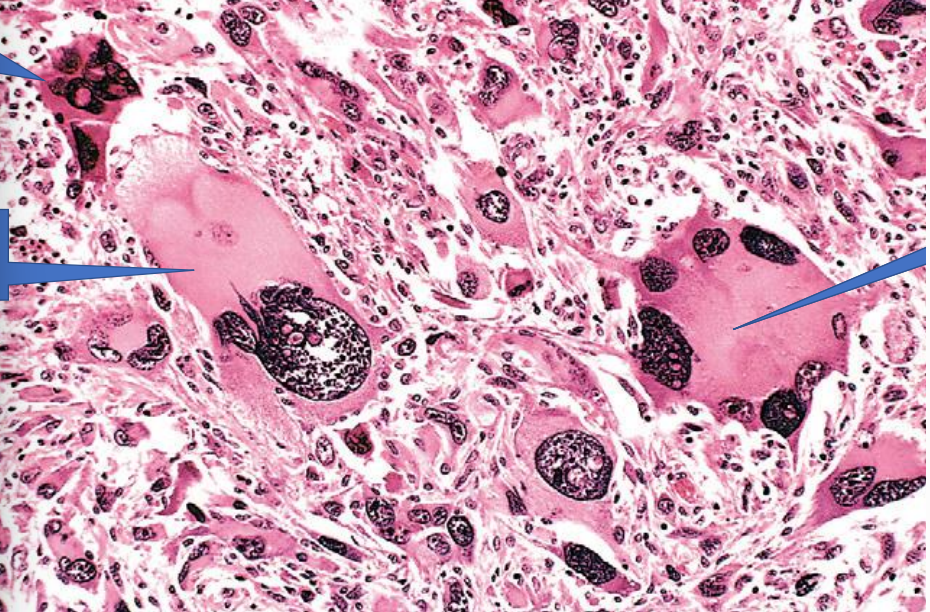

1- Tumor giant cell

2- Cellular and nuclear pleomorphism

3- Tumor giant cell

Squamous cell carcinoma

1- Squamous epithelium

2- Ivasion of Tumor to CT

3- Tumor island with keratin pearl